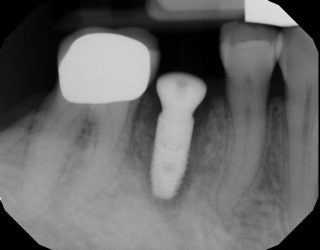

I placed this implant 8 months ago. It was immediate placement. I did the uncovery today. The pre op radiograph shows some loose bone graft. I didn’t really notice anything off upon flapping . ISQ 77. Is it something I should be concerned about?

So I suspect the implant was placed in cortical bone at the top and the lack of blood supply caused this die off. It could also be the lack of KT thickness. This is why I routinely place my implant 2mm subcrestal. At this point I don’t think there’s anything that can be done. It’ll be ok, just something to remember for next time.

It doesn’t look like it will be a problem. Some of the graft turns over into natural bone–but some (like the graft stuck in soft tissue shown above your implant) will not turn over. It’s ok.